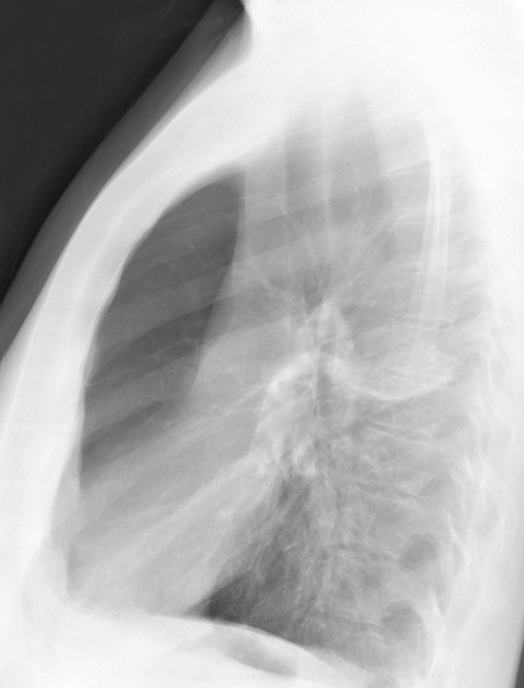

Gallery COPD bulla RUL lat

bulla RUL lat